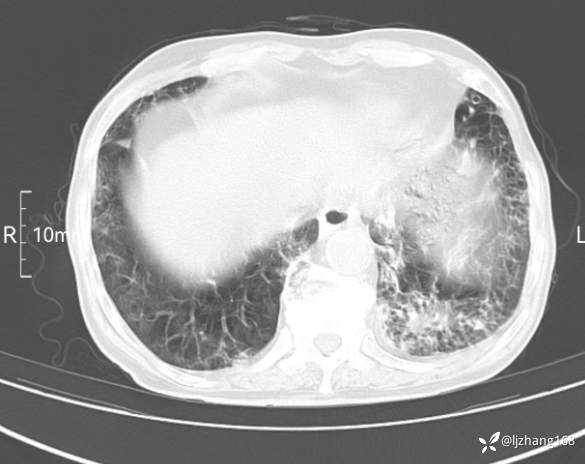

辅助检查:胸部CT:双肺肺气肿,间质性病变,血气分析:PH 7.413, PCO2 29.2mmHg, PO2,81.8mmHg,乳酸 3.3mmol/1,剩余碱-4.0mmol/1,HC03 18.8mmol/1。全血超敏C反应蛋白:超敏C反应蛋白 135.60 mg/L、 白细胞 14x19^9/L,中性粒细胞11.6x10^9/L。